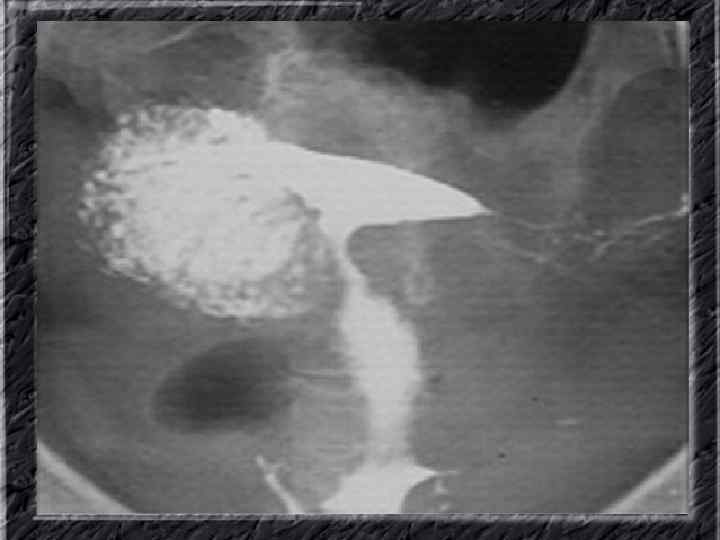

Названия слайдов: • • • Слайд 51. Ультрасонография: интерстициальный и истмический отделы маточной трубы. Слайд 52. Лапароскопия: неизмененная правая маточная труба. Слайд 53. Ультрасонография: многокамерная форма сальпингита. Слайд 54. Лапароскопия: относительно равномерное утолщение маточной трубы при гидросальпинксе. Слайд 55. Лапароскопия: вид маточной трубы при гидросальпинксе. Слайд 56. Гистеросальпингография: неравномерное расширение и деформация маточных труб. Слайд 57. Прервавшаяся трубная беременность: плод; макропрепарат. Слайд 58. Гематосальпингс, развившийся вследствие внутреннего разрыва плодо-вместилища при трубной беременности; макропрепарат. Слайд 59. Лапароскопия: значительное увеличение участка маточной трубы при трубной беременности. Слайд 60. Лапароскопия: скопление крови в полости малого таза в результате трубного аборта.